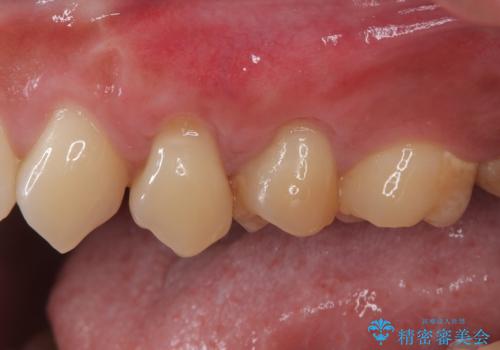

冷たいものがしみる 歯肉移植術で根面被覆